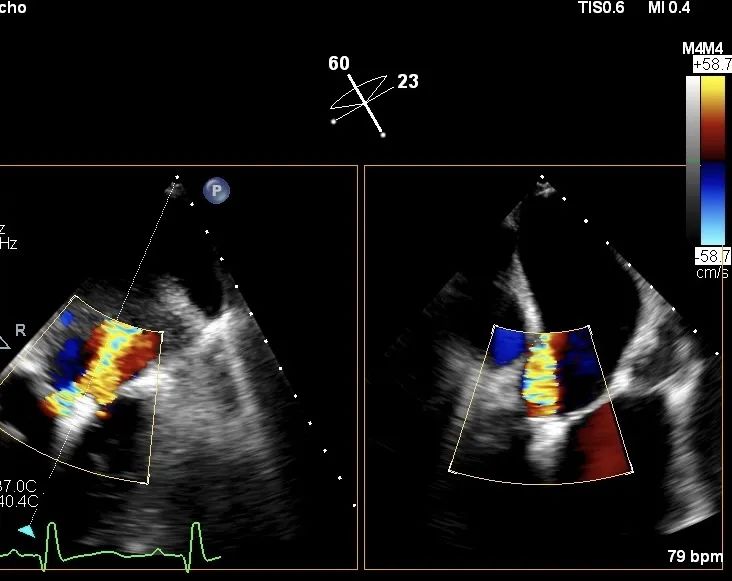

图片

第二枚瓣膜夹夹合后二尖瓣轻度返流